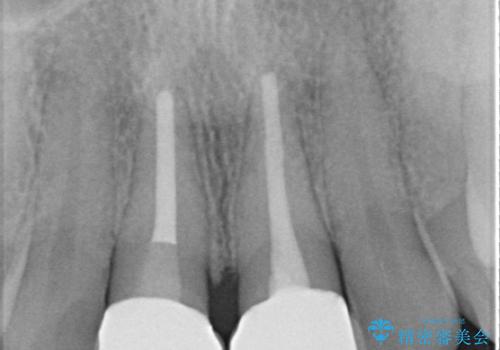

セラミッククラウンで前歯の変色を改善

- 前歯の変色が気になるというご相談をいただき、セラミッククラウンによる治療を行いました。

セラミッククラウンによって前歯の変色が改善され、また歯の形も希望の形態へ修正しました。